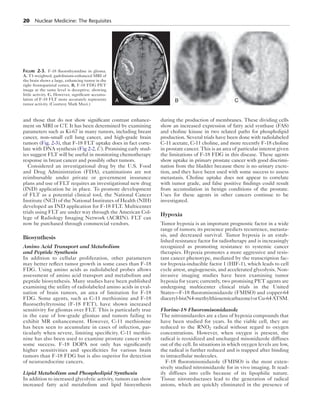

thymidine is also incorporated into DNA via a second

deoxyuridine (Fig. 2-1). Cells and tumors can vary in the use

Figure 2-1. Thymidine as an imaging biomarker. Upper, Thymidine is

taken up into the cell and phosphorylated by thymidine kinase 1 (TK)

in the external salvage pathway. Cells also perform endogenous de novo

synthesis with deoxyuridine (UMP) and the enzyme thymidylate syn-thase

(TS). Lower, F-18–labeled thymidine (FLT) is taken up into the

cell, phosphorylated, and trapped similar to thymidine. However, as the

dashed arrows suggest, FLT is not further metabolized and is not incor-porated

into DNA. FLT-D, difluorothymidine; FLT-M, monofluorothy-midine;

FLT-T, trifluorothymidine; P (circled), phosphate.